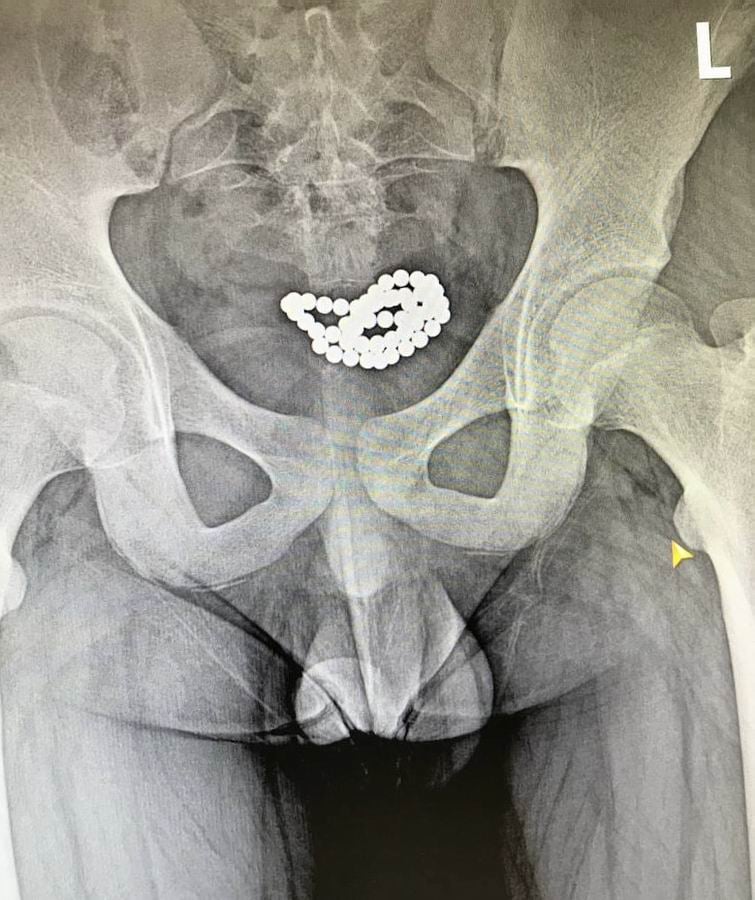

62 и 24 шарика в мочевом пузыре

"В нашем заведении успешно было прооперировано два идентичных случая эвакуации магнитных шариков из мочевого пузыря мальчиков в возрасте 10-15 лет. В обоих случаях была выполнена цистотомия мини-лапаротомным доступом с последующим изъятием 62 и 24 магнитных шариков", - говорится в сообщении.

На фото ниже врачебные снимки, на которых видно, чем чревато неосторожное обращение с игрушками.

Фото: Дети травмировались игрушкой "Неокуб" (Facebook/Волынского областного перинатального центра.)